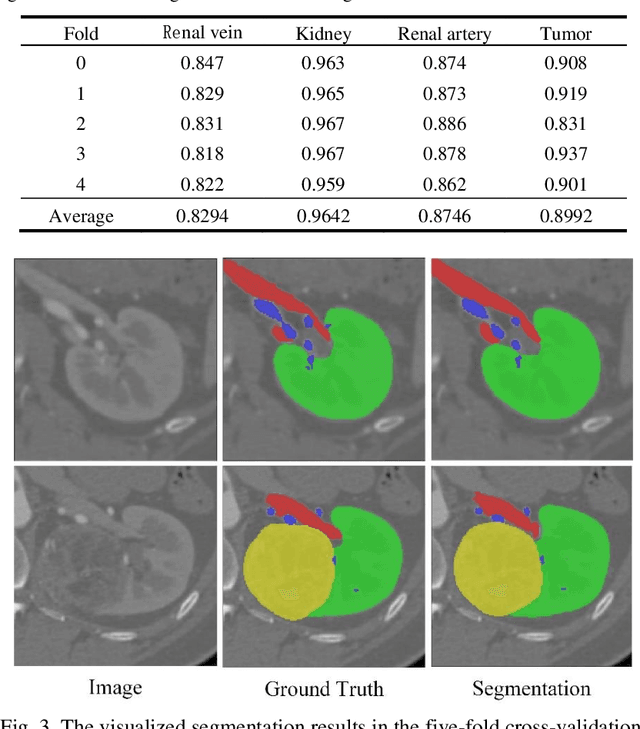

Abstract:Accurate and automated segmentation of multi-structure (i.e., kidneys, renal tu-mors, arteries, and veins) from 3D CTA is one of the most important tasks for surgery-based renal cancer treatment (e.g., laparoscopic partial nephrectomy). This paper briefly presents the main technique details of the multi-structure seg-mentation method in MICCAI 2022 KIPA challenge. The main contribution of this paper is that we design the 3D UNet with the large context information cap-turing capability. Our method ranked eighth on the MICCAI 2022 KIPA chal-lenge open testing dataset with a mean position of 8.2. Our code and trained models are publicly available at https://github.com/fengjiejiejiejie/kipa22_nnunet.